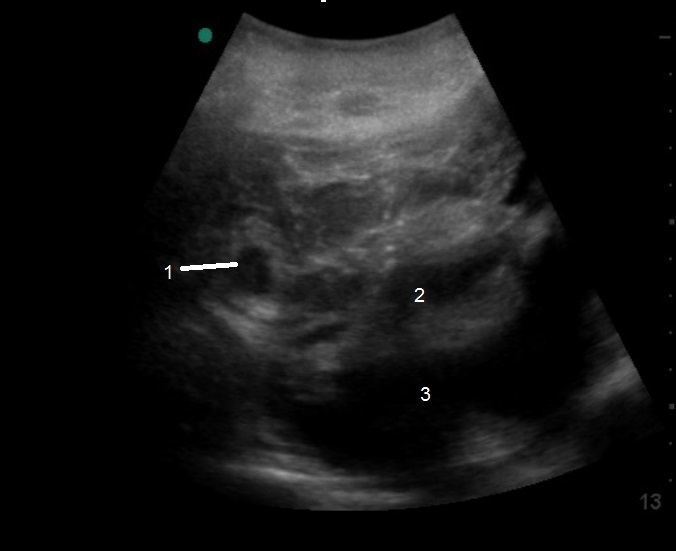

盆腔经腹部 (TA) 异位横切图像

异位

空子宫

游离液体